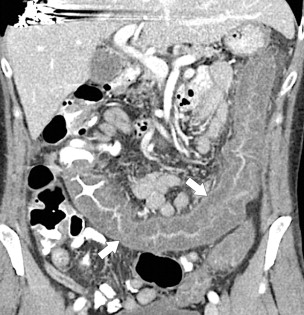

Often the infectious etiology cannot be determined by imaging alone because all the agents cause nonspecific colonic wall thickening and some cause a pancolitis, including Escherichia coli (although this colitis can be severe [ Fig. 5-47 ]) and those involved in traveler’s diarrhea ( Fig. 5-48 ). Other pathogens tend to affect specific colonic areas more than others. Campylobacter sp. is sometimes indistinguishable from UC ( Fig. 5-49 ), but is often confined to the rectum. Other rectal colitides include gonococcal and herpes colitis. Shigella sp. primarily affects the left side of the colon, whereas Salmonella typhi, tuberculosis, Yersinia, and amebiasis are focally confined to the ileocecal region with or without local adenopathy.

Figure 5-47, Axial ( A ) and coronal ( B ) contrast-enhanced CT in a 12-year-old boy with marked colonic thickening ( arrows ), particularly the right colon due to E. coli colitis.

Figure 5-48, Axial ( A ) and coronal ( B ) contrast-enhanced CT in a 64-year-old woman with pancolitic mucosal thickening ( arrows ) due to traveler’s diarrhea.